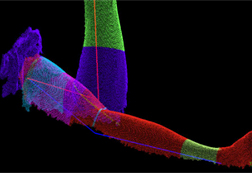

ハンディ3Dスキャナーは静止した物だけでなく、動く(移動する)対象物も撮影して、画面ごとにサーフェースモデルを作成します。変化する体(腕や背中など)を撮影し、リハビリでの改善状況の把握に役立てます。また、部品の変位移動量(振動するケーブルや部品の挙動など)を3D解析することで、これまで実行できなかった製品のシミュレーションが可能となります。

特集 ハンディ3Dスキャナーをリハビリで利用する

1. 従来のマニュアル測定方法に代え、非接触ハンディ3Dスキャナーで関節の曲がり状態を調べる。